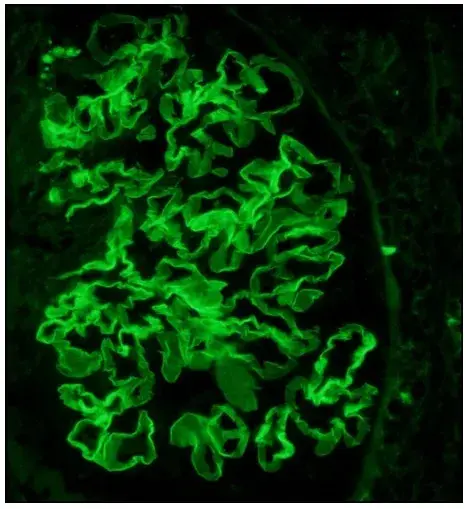

Caso muy ilustrativo publicado en Kidney 360 (enlace). Paciente de sexo femenino de 43 años con antecedentes de nefritis lúpica (NL) proliferativa durante 13 años. La paciente tenía un historial de enfermedad grave, con múltiples tratamientos que incluyeron infusiones de metilprednisolona y ciclofosfamida debido al compromiso del sistema nervioso central (SNC) y de la NL.